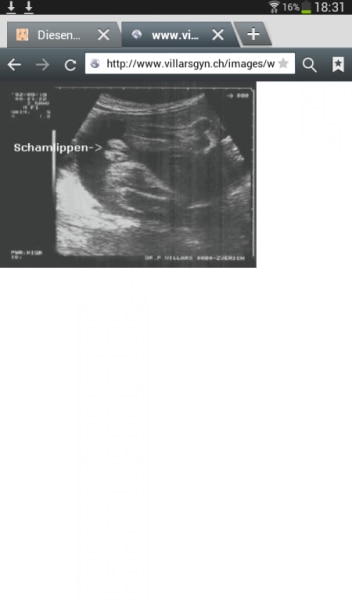

Die Vulva ist in diesem Stadium noch geschwollen und bildet sich zurück. links und rechts sind die Labien, mittig der Strich der Scheideneingang. Ich würde im Expertenforum fragen.

Bild zu

Ich sehe die 2 hodensäcke (die im übrigen auch unten zusammen gehen) und dann dazwischen den Penis. Für mich sieht es nach 3 teilen aus. Ja die Vulva ist geschwollen, aber eben auch der hodensack. Und bei uns war zwischen den schamlippen immer ein strich. Den sehe ich hier nicht. Darum rippe ich auf junge.